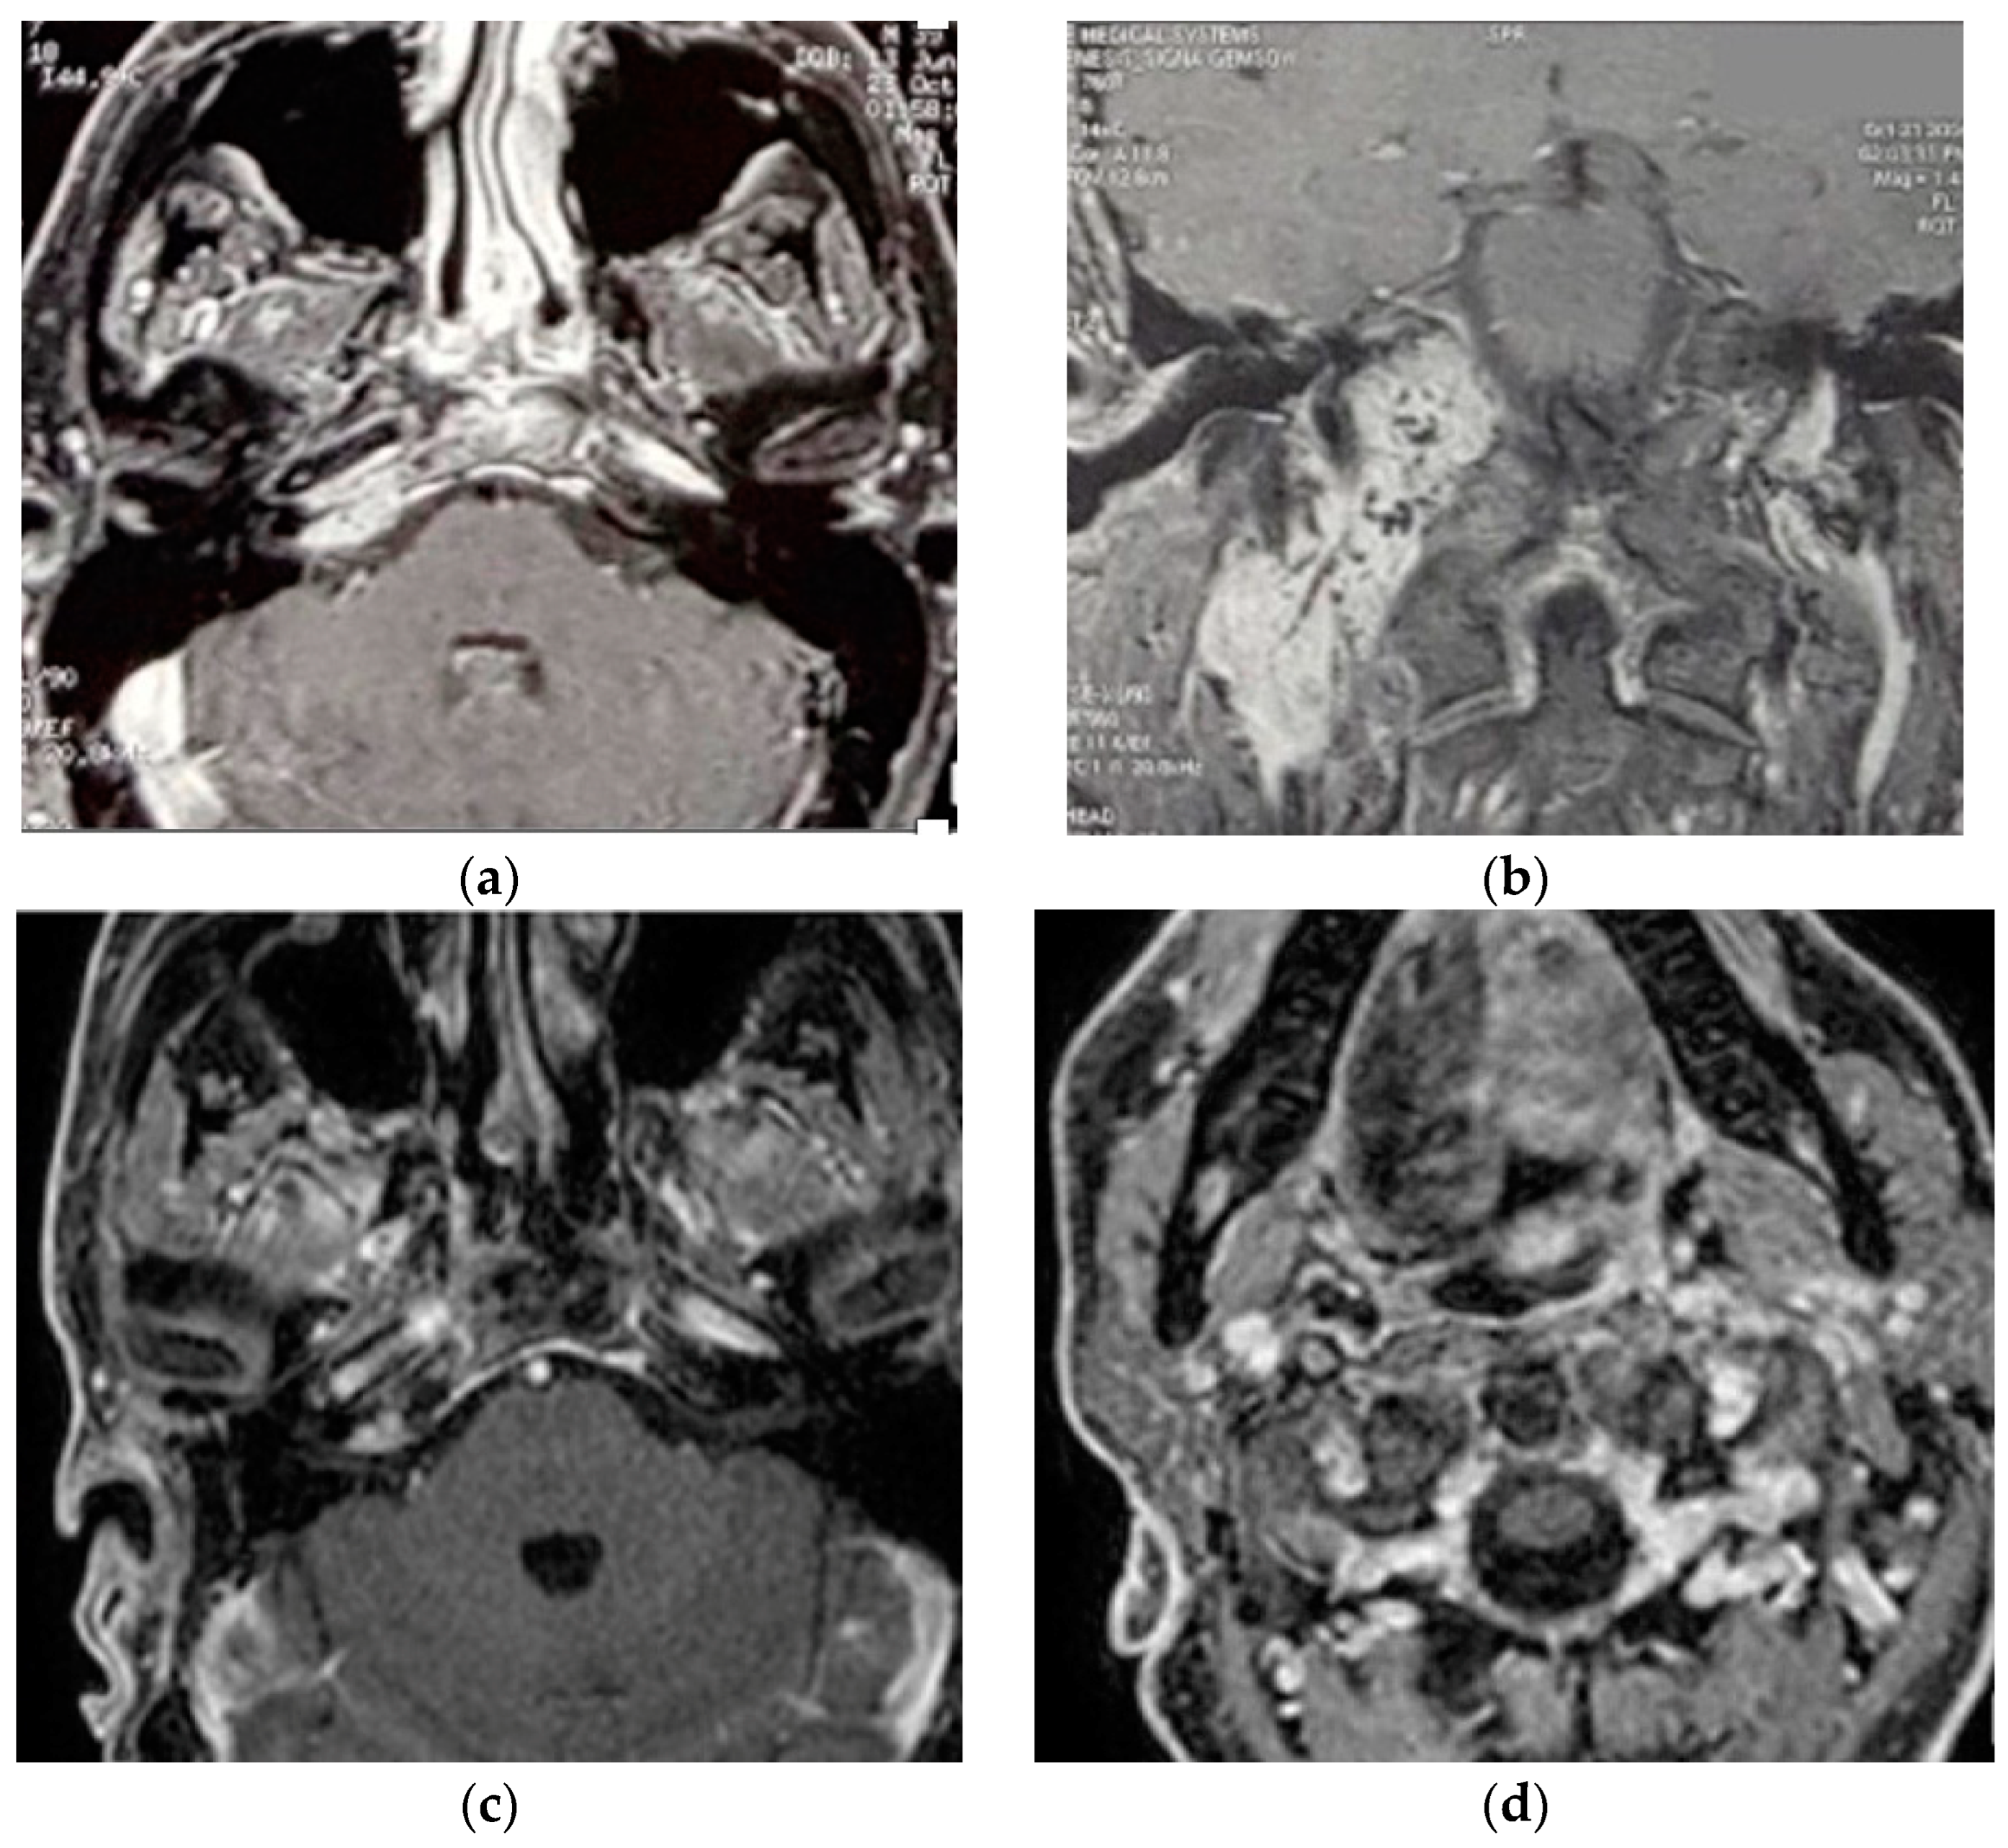

5.6. Case 6: (C4Di2Vi)